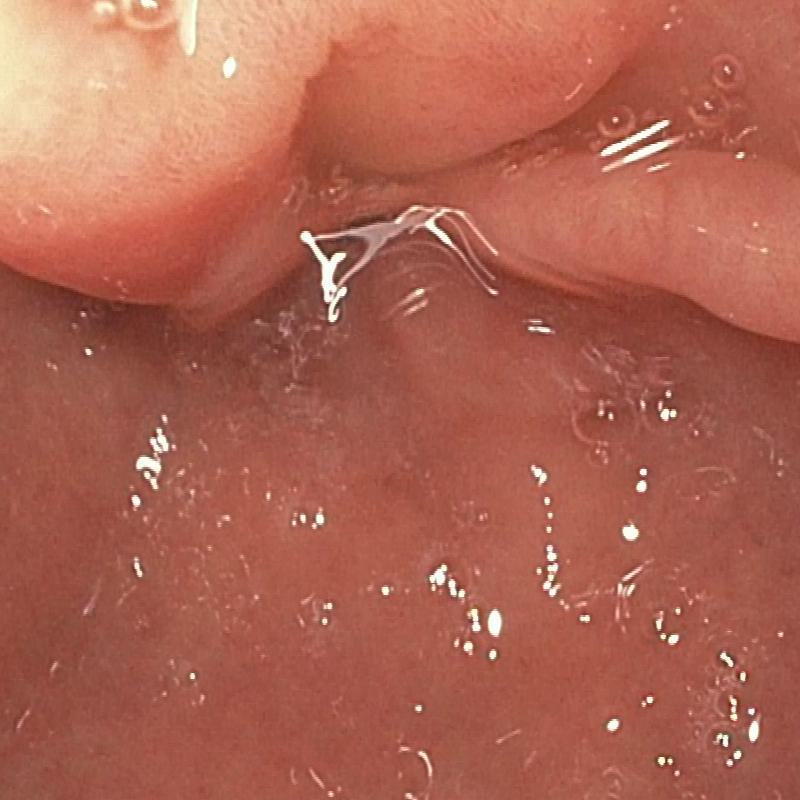

| (a) Input | (b) LIME | (c) HDRNet | (d) LECCM | (e) SwinIR | (f) NAFNet | (g) EndolMLE | (h) Ours | (i) GT |

The proposed method was evaluated on a synthetic dataset. All deep learning-based methods were fine-tuned based on E-kvasri. Figure 2 presents sample results of the proposed method and comparative methods on four endoscopic images from the E-kvasri.